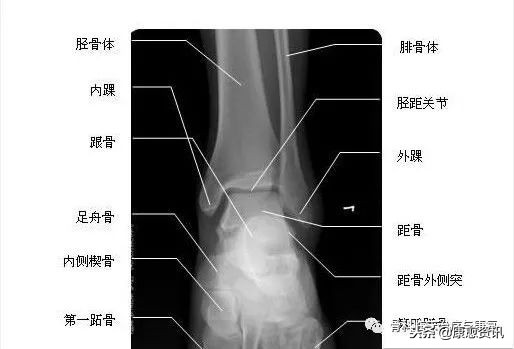

踝部骨折包括胫腓骨下段骨折、内外后踝骨折、距骨骨折、跟骨骨折、舟状骨骨折、跖骨骨折,不包括踝关节置换。